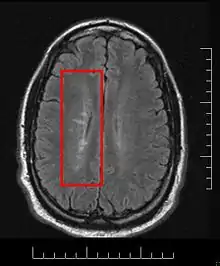

Multiple sclerosis is considered a disease of the white matter because normally lesions appear in this area, but it is also possible to find some of them in the grey matter.[30]

Using high field MRI system, with several variants several areas show lesions, and can be spacially classified in infratentorial, callosal, juxtacortical, periventricular, and other white matter areas.[31] Other authors simplify this in three regions: intracortical, mixed gray-white matter, and juxtacortical.[32] Others classify them as hippocampal, cortical, and WM lesions,[33] and finally, others give seven areas: intracortical, mixed white matter-gray matter, juxtacortical, deep gray matter, periventricular white matter, deep white matter, and infratentorial lesions.[34] The distribution of the lesions could be linked to the clinical evolution[35]

Due to the distribution of the lesions, since 1916 they are also known as Dawson's fingers.[40] They appear around the brain blood vessels.

Most MS lesions are isointense to white matter (they appear bright) on T1-weighted MRI, but some are "hypointense" (lower intensity). These are called "black holes" (BH). They appear specially in the supratentorial region of the brain.